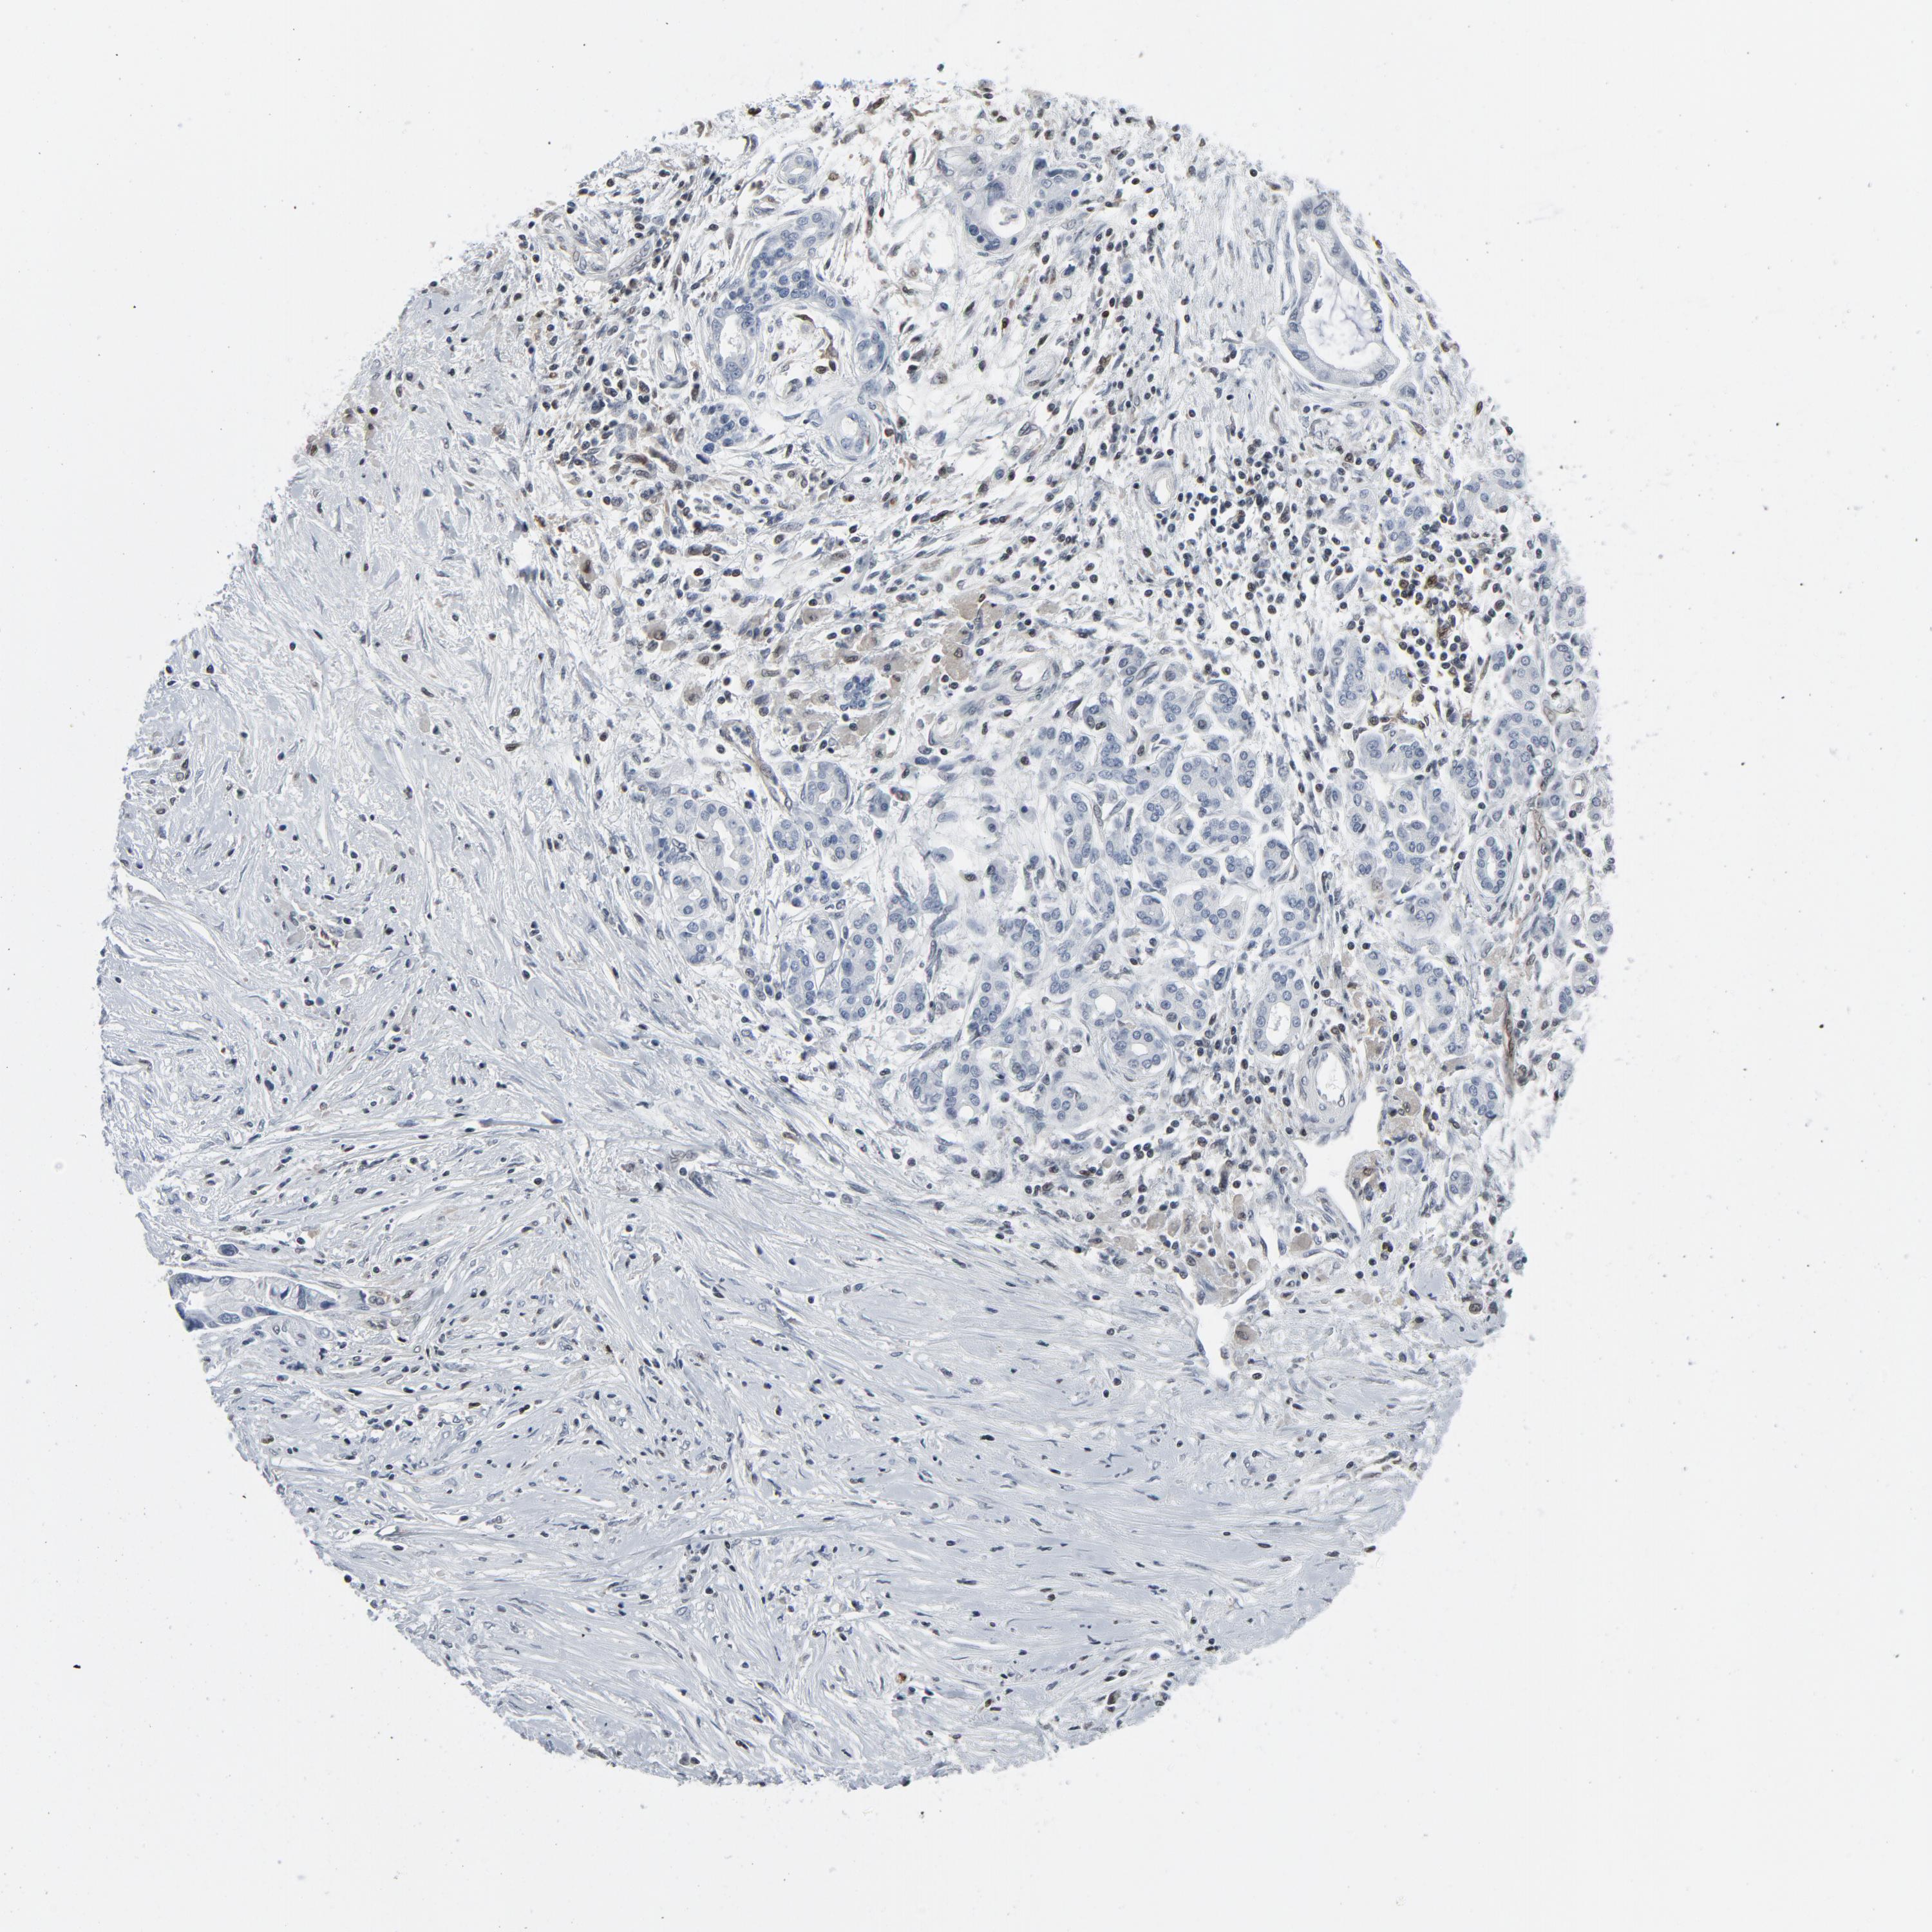

PANCREATIC CANCER - Protein expressioni

A mouse-over function shows sample information and annotation data. Click on an image to view it in a full screen mode. Samples can be filtered based on level of antibody staining by selecting one or several of the following categories: high, medium, low and not detected. The assay and annotation is described here.

Note that samples used for immunohistochemistry by the Human Protein Atlas do not correspond to samples in the TCGA dataset.

Antibody stainingi

Antibody staining in the annotated cell types in the current human tissue is reported as not detected, low, medium, or high, based on conventional immunohistochemistry profiling in selected tissues. This score is based on the combination of the staining intensity and fraction of stained cells.

Each image is clickable and will lead to virtual microscopy that enables deeper exploration of all samples and also displays staining intensity scores, fraction scores and subcellular localization as well as patient and tissue information for each sample.

HPA027873

HPA042128

HPA049883

HPA051156

CAB003860